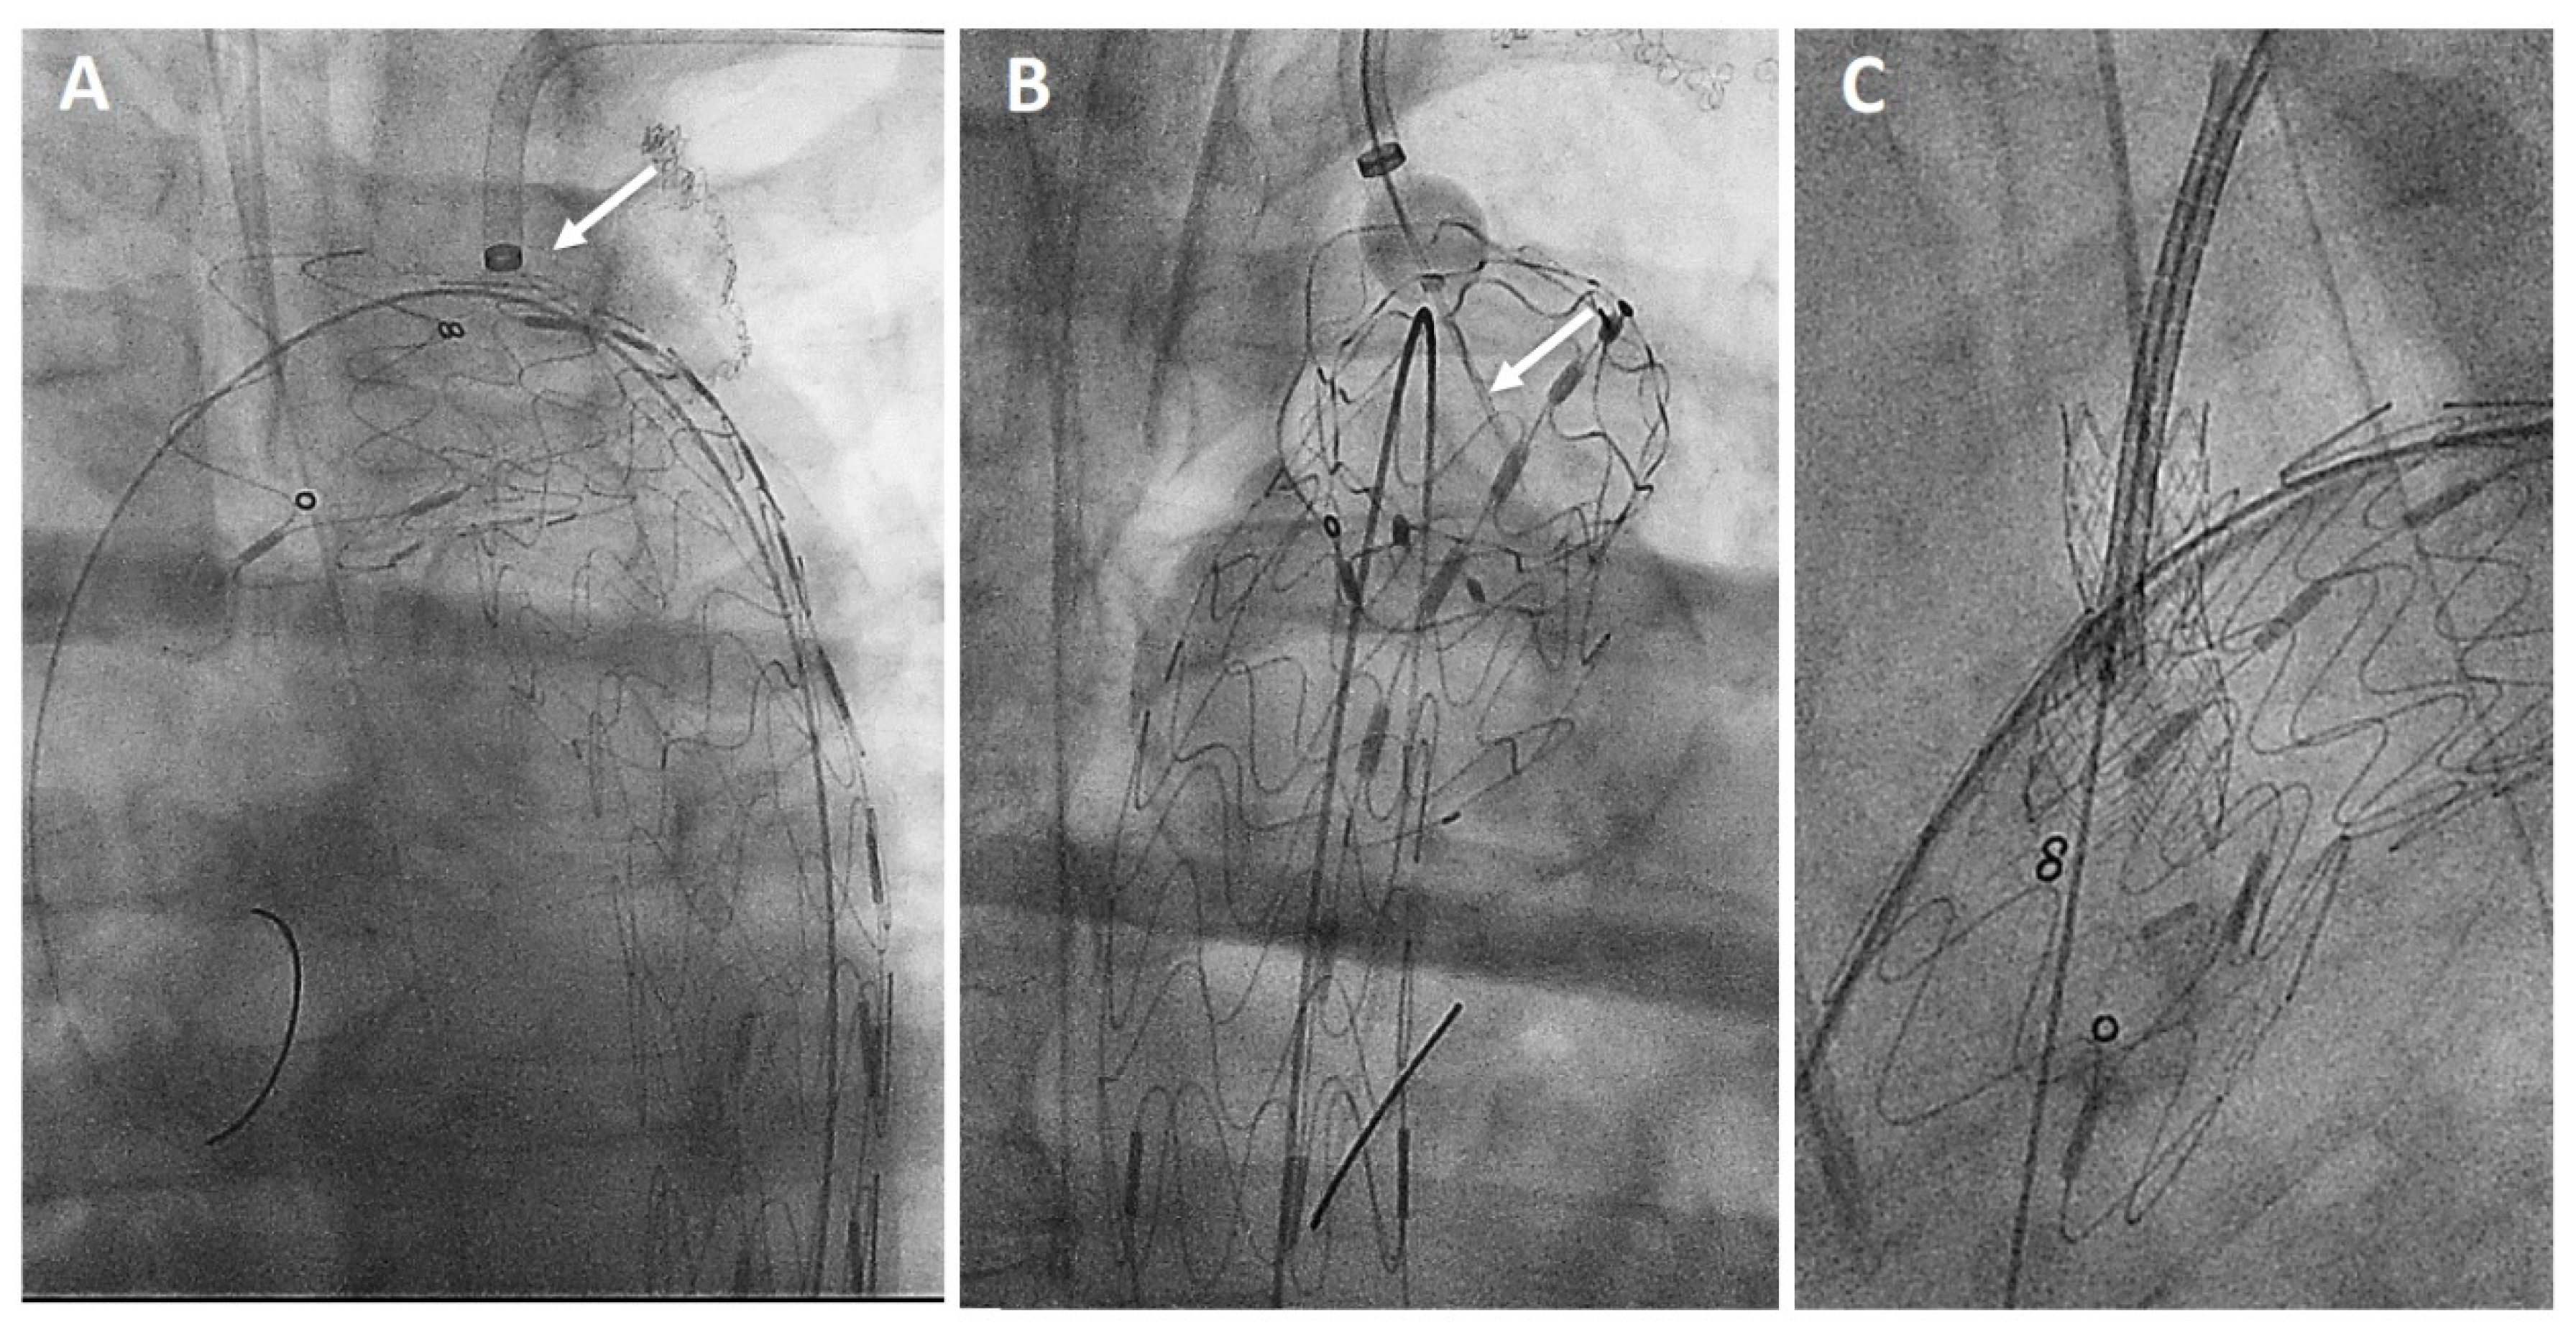

2.2. Device Description and IFUs

- Wang, L.; Zhou, X.; Guo, D.; Hou, K.; Shi, Z.; Tang, X.; Fu, W. A New Adjustable Puncture Device for In Situ Fenestration During Thoracic Endovascular Aortic Repair. J. Endovasc. Ther. 2018, 25, 474–479. [Google Scholar] [CrossRef] [PubMed]

- Shu, X.; Xu, H.; Wang, E.; Wang, L.; Guo, D.; Chen, B.; Fu, W. Midterm Outcomes of an Adjustable Puncture Device for In Situ Fenestration During Thoracic Endovascular Aortic Repair. Eur. J. Vasc. Endovasc. Surg. 2022, 63, 43–51. [Google Scholar] [CrossRef] [PubMed]

- Xiang, Y.; Qiu, C.; He, Y.; Li, D.; Shang, T.; Wu, Z.; Zhang, H. A Single Center Experience of In Situ Needle Fenestration of Supra-aortic Branches During Thoracic Endovascular Aortic Repair. Ann. Vasc. Surg. 2019, 61, 107–115. [Google Scholar] [CrossRef]

- Yu, Z.; Hu, S.; Wang, D.; Yang, T.; Lang, D. Early and midterm outcomes of in situ fenestration via adjustable puncture needle for Ankura aortic stent graft: A single-center experience. Vascular, 2023; online ahead of print. [Google Scholar] [CrossRef]